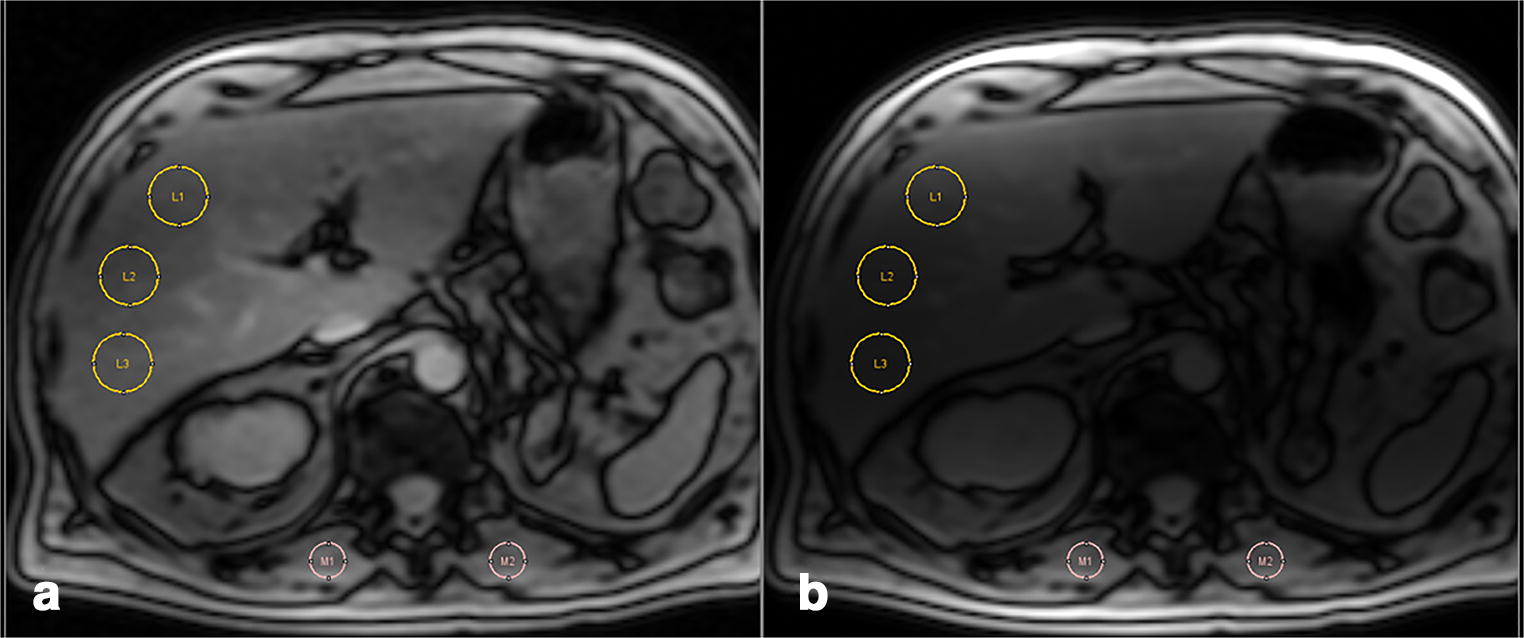

Quantification of liver iron concentration by MRI. (A) Important Liver Iron Quantification Mri T2 relaxometry and signal intensity ratio. Advanced mr imaging for quantification of liver iron. Detection and quantification of liver iron content. This review describes mr imaging techniques for liver iron quantification and provides an overview of. This article is a guide for. While detection of liver iron using qualitative mri is possible, qualitative mri methods do not. There are two. Liver Iron Quantification Mri.

Figure 1 from Liver Iron Quantification with MR Imaging A Primer for Liver Iron Quantification Mri T2 relaxometry and signal intensity ratio. There are two principle methods of liver iron quantification by mri: Detection and quantification of liver iron content. This article is a guide for. Advanced mr imaging for quantification of liver iron. This review describes mr imaging techniques for liver iron quantification and provides an overview of. Based on this summary, expert consensus panel.. Liver Iron Quantification Mri.